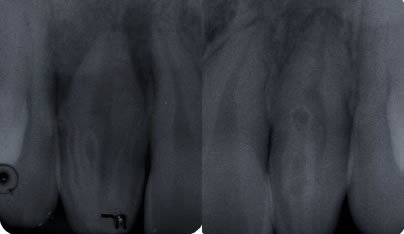

Clinically, dens invaginatus appears in the tooth crown at the site of an anatomical lingual pit susceptible to caries.(3) Radiographically, it shows a radiopaque invagination, equal in density to enamel, extending from the cingulum into the root canal.(1) The defects may vary in size and shape from a loop like, pear-shaped or slightly radiolucent structure to a severe form resembling a “tooth within a tooth”.(4) It can be identified easily because infolding of the enamel lining is more radiopaque than the surrounding tooth structure.(1)

Case Description: The 17 y.o. Asian, female patient presented to our office with a complaint of “my dentist told me I don’t have a root, that it was fused when I was born. I had pain one year ago and then again two months ago. My face was swollen and the dentist put me on antibiotics.” She was referred for teeth #6 & #7. Tooth #7 did not respond to cold, but all other teeth tested normally. Both #7 & #10 presented with dens invaginations. The lamina dura and periodontal ligament(PDL) were not intact around #7. The lamina dura was intact around #10 and the PDL was widened. A diffuse radiolucency was noted around the apices of #7, which also appeared to encroach upon #6 and #8. A widened PDL was noted around #6. Tooth #7 was diagnosed as: necrotic pulp and asymptomatic apical periodontitis. Tooth #10 was diagnosed as: normal pulp, normal periodontium.

Figure 1: Periapical radiograph showing a maxillary right lateral incisor with four dens invaginatus Figure 2: Periapical radiograph showing a maxillary left lateral incisor with one dens invaginatus